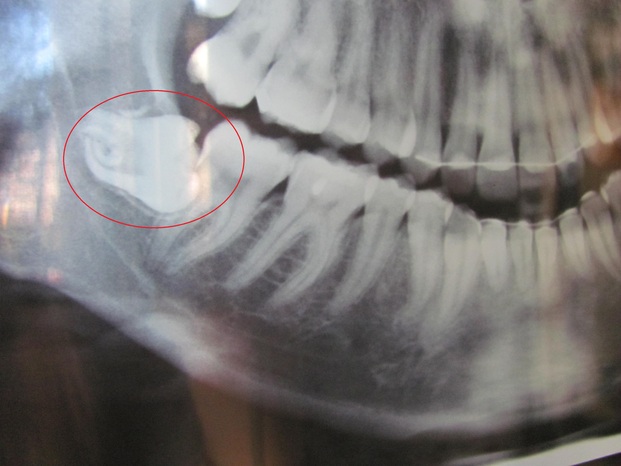

Il dente incriminato, lo vedete? E' in orizzontale.

Avendo la bocca piccola, non è riuscito ad uscire ed è cresciuto in quel modo.

Il mio nuovo dentista non vuole estrarmelo, perché essendo immerso completamente nella gengiva serve una vera e propria operazione. Io poi non me ne intendo molto.

Ha detto che potrei perdere la sensibilità di tutta quella parte della bocca. Se non lo tolgo, invece, mi farà storcere tutti gli altri denti e mi porterà mal di testa ed altri problemi.

Intanto ho i "denti storti", ma veramente. Non un pochino, come spesso capita a coloro che non hanno portato l'apparecchio dentale, i miei sono proprio in orizzontale!